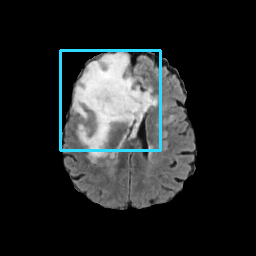

Refer to caption

(a) CT images.

(b) MRI images.

Figure 6: Lossy compression based attack on CT images (a) and MRI images (b) with a specific channel numbers (C8050\mathrm{C^{50}_{80}}) for the EP and IT Scenarios. StolenEPD1\mathrm{Stolen}^{\mathrm{D1}}_{\mathrm{EP}} denotes the decompressed images in the EP Scenario with a reduced D1 decoder.

Compression-Fidelity Compromise. Based on the previous results, we have selected the decoder D1D1 and the configuration of the latent and hyperlatent variables C8050\mathrm{C^{50}_{80}}, as the optimal architecture of the HiFiC encoder-decoder pair. In Fig. 6, we display more specifically the compression and reconstruction quality performances. In terms of reconstruction quality, we obtain a PSNR of approximately 40 for CT images and around 38 for MRI images while the MS_SSIM values are close to 1. This indicates an excellent perceptual quality of the reconstructed images that are hardly discernible from the original ones. In terms of compression efficiency, the Pratio\mathrm{P}_{\mathrm{ratio}} for CT images is approximately 0.015, indicating that the lossy image compression-based attack generated compressed images are 67 times smaller than those produced by the lossless zipped image compression-based attack. For MRI images, the Pratio\mathrm{P}_{\mathrm{ratio}} is around 0.12, 10 times higher than that of CT images, which can be attributed to the presence of a large uniform background in the skull-stripped original MR images.

A visual comparison between target and stolen images is available in Fig. 7. We observe that the stolen images from IT Scenario closely resemble the input ones, particularly in the tumor regions, whereas stolen images from EP Scenario exhibit blurring artifacts in finer details. In both cases, the stolen images reconstructed by D1D1 demonstrate a comparable quality to those reconstructed by DD, thus further confirming the effectiveness of the reduced decoder D1D1.